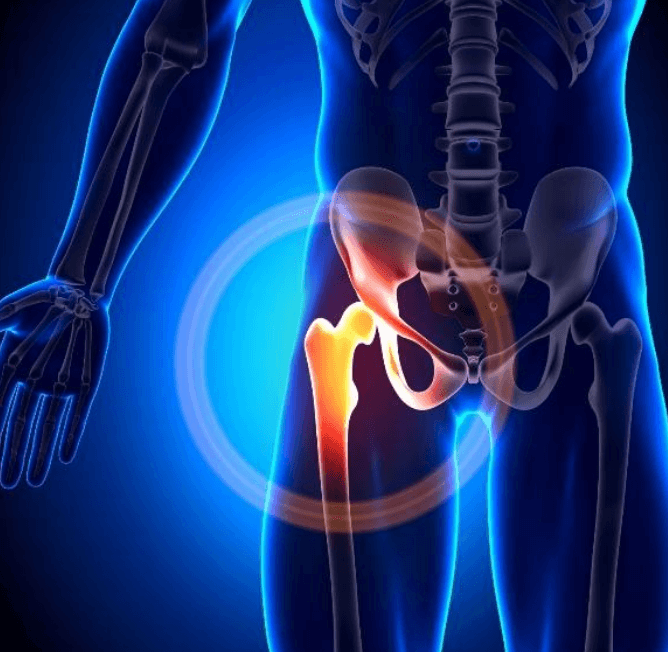

What Is Arthritis? Arthritis refers to inflammation of the joints. It’s not a single condition but a broad term thatcovers over 100 different types. The most common include: The main symptoms of arthritis include: If left untreated, arthritis can significantly impact your mobility and independence. This is where physiotherapy plays a crucial role. How Physiotherapy […]